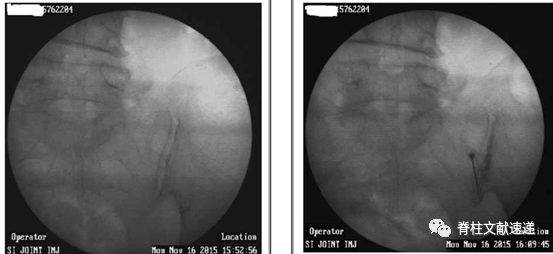

骶髂关节阻滞用于鉴别骶髂关节导致的腰骶部疼痛。具体操作如下。

6.1 俯卧位,常规消毒,定位。以目标骶髂关节为中心透视。

6.2 穿刺针向外向尾倾斜,向骶髂关节间隙穿刺。

6.3 先注入0.5ml造影剂,确认后注入局麻药物。